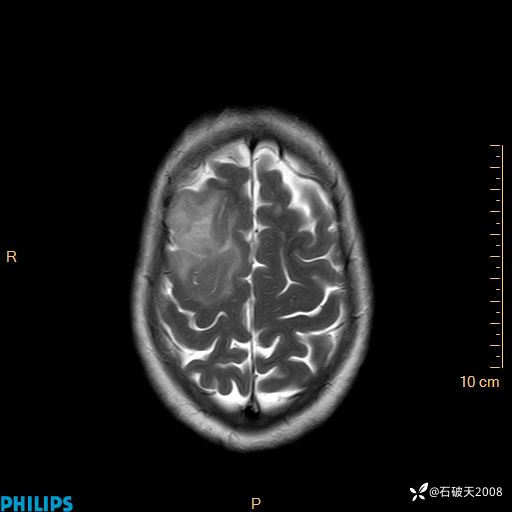

2020.11.14MR

T2

T1